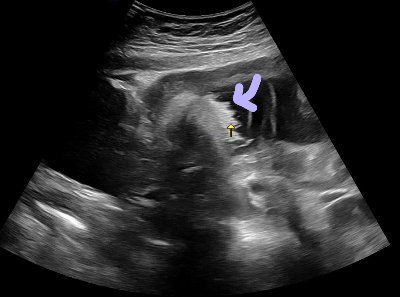

정기 초음파 (이번주차 보험적용)로 머리 둘레, 배둘레, 다리길이, 신장 등등 봐주셨어요.

가장 기억에 남는건 머리카락ㅋㅋ

양수안에서 하찮게 흔들리고 있는 머리카락이 엄청 귀엽더라구요.